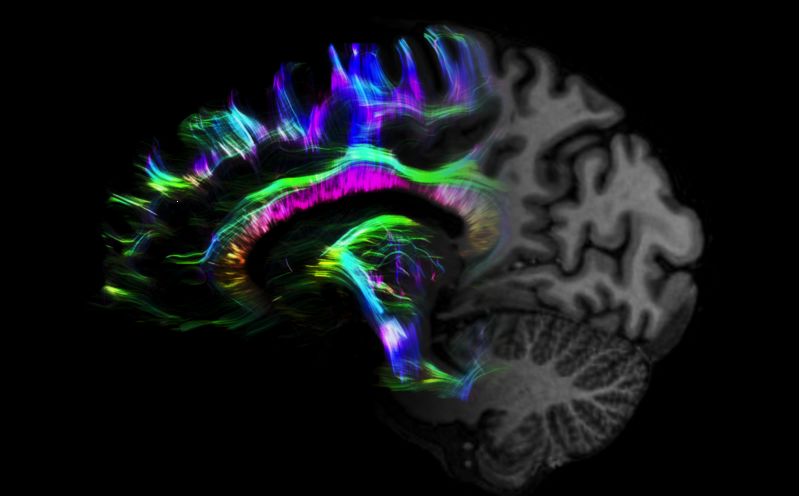

但近年來(lái),西門(mén)子與科研機(jī)構(gòu)共同研究發(fā)現(xiàn),7T提供了數(shù)倍于傳統(tǒng)3T磁共振的信噪比和空間分辨率,在神經(jīng)、血管、腫瘤、骨關(guān)節(jié)等多個(gè)方面都會(huì)帶來(lái)全新的突破性進(jìn)展。尤其是在目前常規(guī)影像設(shè)備難以診斷的神經(jīng)退行性疾病如阿茲海默氏病、帕金森病等疾病的發(fā)病機(jī)理、早期診斷、治療方案確定以及治療效果評(píng)估上,有著極大的潛力。

MAGNETOM Terra在業(yè)界首次實(shí)現(xiàn)了兩倍于傳統(tǒng)7T的超強(qiáng)梯度性能,實(shí)現(xiàn)超快速、超高效、超高分辨功能磁共振成像。如此高性能的梯度系統(tǒng)無(wú)論對(duì)于科研還是臨床都帶來(lái)了更多可能。

1毫米的各向同性分辨率DTI:神經(jīng)纖維束的交叉細(xì)節(jié)顯示

0.8毫米的各向同性分辨率:精確劃分灰質(zhì)和白質(zhì)

0.8毫米的各向同性分辨率:超精細(xì)的解剖細(xì)節(jié),例:小腦的精細(xì)結(jié)構(gòu)